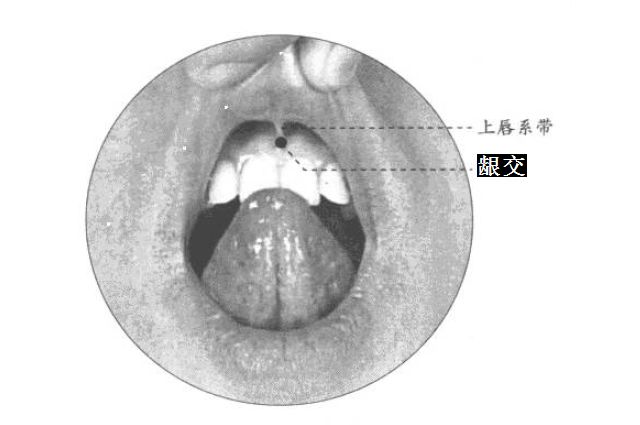

部位:在上唇内,上唇系带与上牙龈的交点。

取穴:正坐仰.头,提起上唇,于上唇系带与齿龈的移行处取穴。